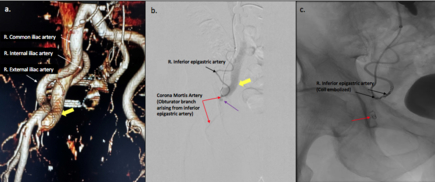

A 71-year-old male underwent pulmonary vein isolation for persistent AF. The right femoral vein was accessed using ultrasound guidance and 3 sheaths were placed after which intravenous heparin was administered. At the end of the case, protamine was given for heparin and a figure of 8 suture was placed after sheath removal. Six hours post procedure, a soft 2.5 cm right groin hematoma was noted, that was treated conservatively with manual pressure and pressure dressing overnight. The patient was discharged home next day but returned one week later with continued groin pain and swelling. Examination revealed a moderate groin hematoma, ecchymosis and a loud right femoral bruit. Duplex ultrasound demonstrated a fistula between the right external iliac artery and vein with potential pseudoaneurysm at the fistula site. CT angiogram of the abdomen and pelvis showed a pseudoaneurysm of a distal branch of the external iliac artery arising from the inferior epigastric artery and an AVF (Fig 1a). Selective arteriogram was performed via left groin access, which confirmed the above findings as a result of injury to the corona mortis (Fig 1b). Coil embolectomy of the right inferior epigastric artery and the obturator branch up to the respective origins was performed with resolution of the fistula (Fig 1c). The patient was discharged home and oral anticoagulation therapy was restarted 24 hours later. He recovered well with no further sequelae.

The corona mortis artery is a common vascular variant which may be a source of bleeding complications during groin injury or during vascular groin access. Familiarity with this variant allows its consideration in the differential diagnosis of post procedural groin hematoma which ensures rapid diagnosis and appropriate management.